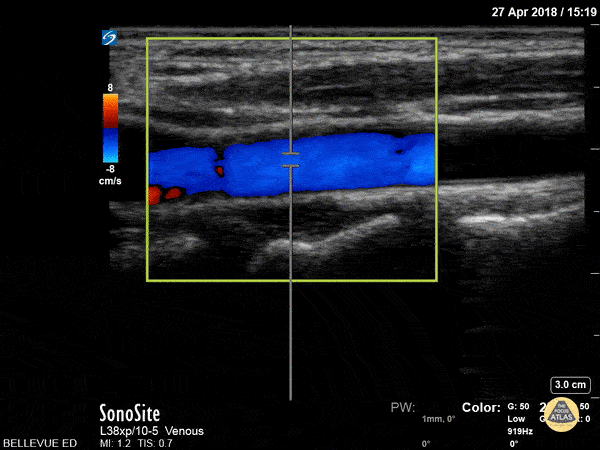

The common carotid artery in long axis with color doppler overlay. On the far left of the screen the wide carotid bulb is visible. Hannah Kopinksi and Dr. Lindsay Davis - NYU Emergency Medicine